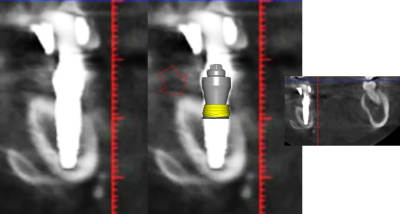

1 se baser sur la pano pour en tirer des conclusions est une erreur de débutant

2 sur les coupes scanner une partie du col est infra osseuse et l'autre non

> 1 se baser sur la pano pour en tirer des conclusions est une erreur de débutant

>

> 2 sur les coupes scanner une partie du col est infra osseuse et l'autre non

mais posit... y'a que toi qui pense que l'implant est aussi enfoui... ca saute aux yeux que tu fais tout pour grater 1mm d'enfouissement... pour qu'ils paraissent pas si mal posé que ca...

avec, par exemple, ton implant de 10mm qui est contenu dans 9mm... t'es le Gérard Majax des guides chir.

comme ici... si e carré fait 4,5 alors l’implant ne fait pas 10 mais moins de 9...

Tout comme l’autre implant pas 11,5 mais 10,3

heureusement que ta méthode est "précise" ;)

mais si tu t'intéressais un peu à la littérature tu saurais que ce n'est pas un problème dans ce cas clinique et tu ne serais pas obligé de mentir en dessinant n'importe quoi

En traçant le col de l'implant comme tu le fais tu ne tiens pas compte que le pilier fait 4,5 mm de hauteur, normalement tu devrais arriver à le comprendre tout seul !

Pour le reste de la discussion que le col ne soit tout infra osseux oui mais pas "5 spires" et tout les implants sont en bi corticale. Lorsque tu dis à quelqu'un qu'il est de mauvaise foi vérifie en premier tes arguments. Pour le col dans un cas comme celui là ce n'est pas un problème.

Dans ce cas l'épaisseur du sulcus est de 8 à 12 mm

L'enfouissement des implants était programmé pour stopper à 50 Ncm